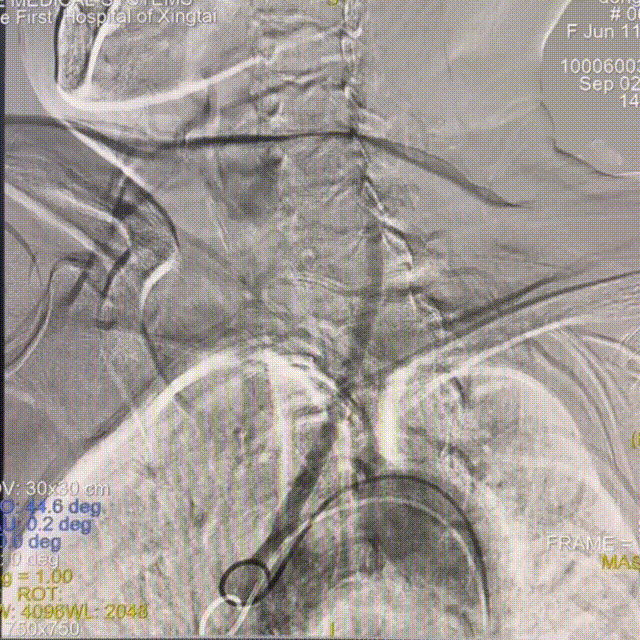

通路建立:患者主动脉弓造影显示Ⅲ型弓,病变为右侧大脑中动脉栓塞,故选择赛诺神畅APEX TRA GC™5F-130 SIM2导引导管同轴长鞘建立通路。

动脉长鞘怎么置入一技之“长”丨经桡及经股困难入路应用赛诺神畅APEX TRA GC™导引导管建立通路病例合集_https://www.jmylbn.com_新闻资讯_第7张

Ⅲ型弓

动脉长鞘怎么置入一技之“长”丨经桡及经股困难入路应用赛诺神畅APEX TRA GC™导引导管建立通路病例合集_https://www.jmylbn.com_新闻资讯_第8张

长SIM2导管成袢

动脉长鞘怎么置入一技之“长”丨经桡及经股困难入路应用赛诺神畅APEX TRA GC™导引导管建立通路病例合集_https://www.jmylbn.com_新闻资讯_第9张

顺利超选入无名动脉

跟进长鞘至右侧颈内动脉,输送068抽吸导管,释放6*30mm 取栓支架。